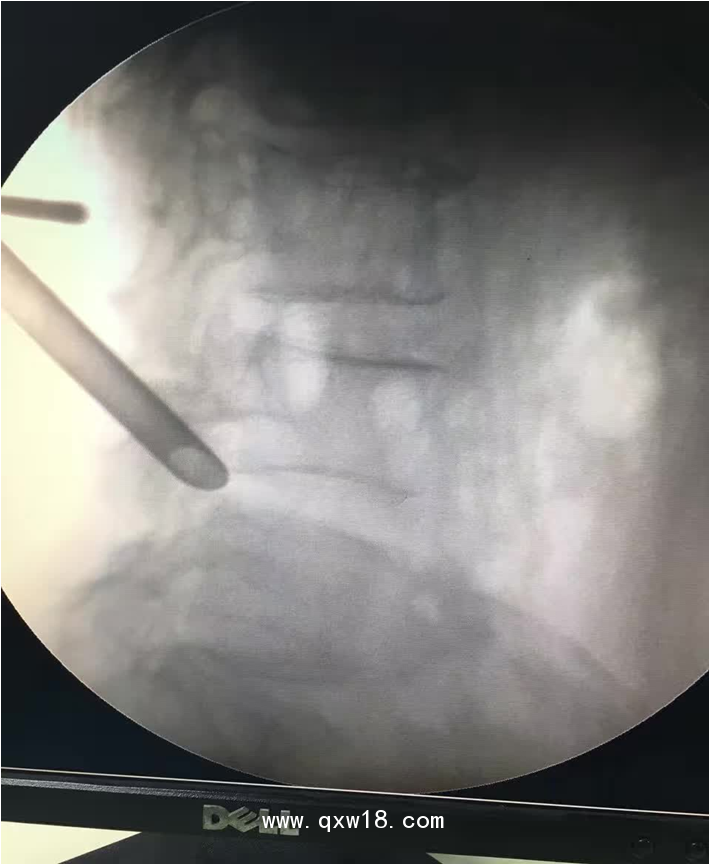

椎間孔鏡品牌椎間孔鏡椎間孔鏡技術(shù)椎間孔鏡培訓(xùn)產(chǎn)品說明:

portant; word-wrap: break-word !important;">椎間孔鏡手術(shù)圍手術(shù)期注意事項: